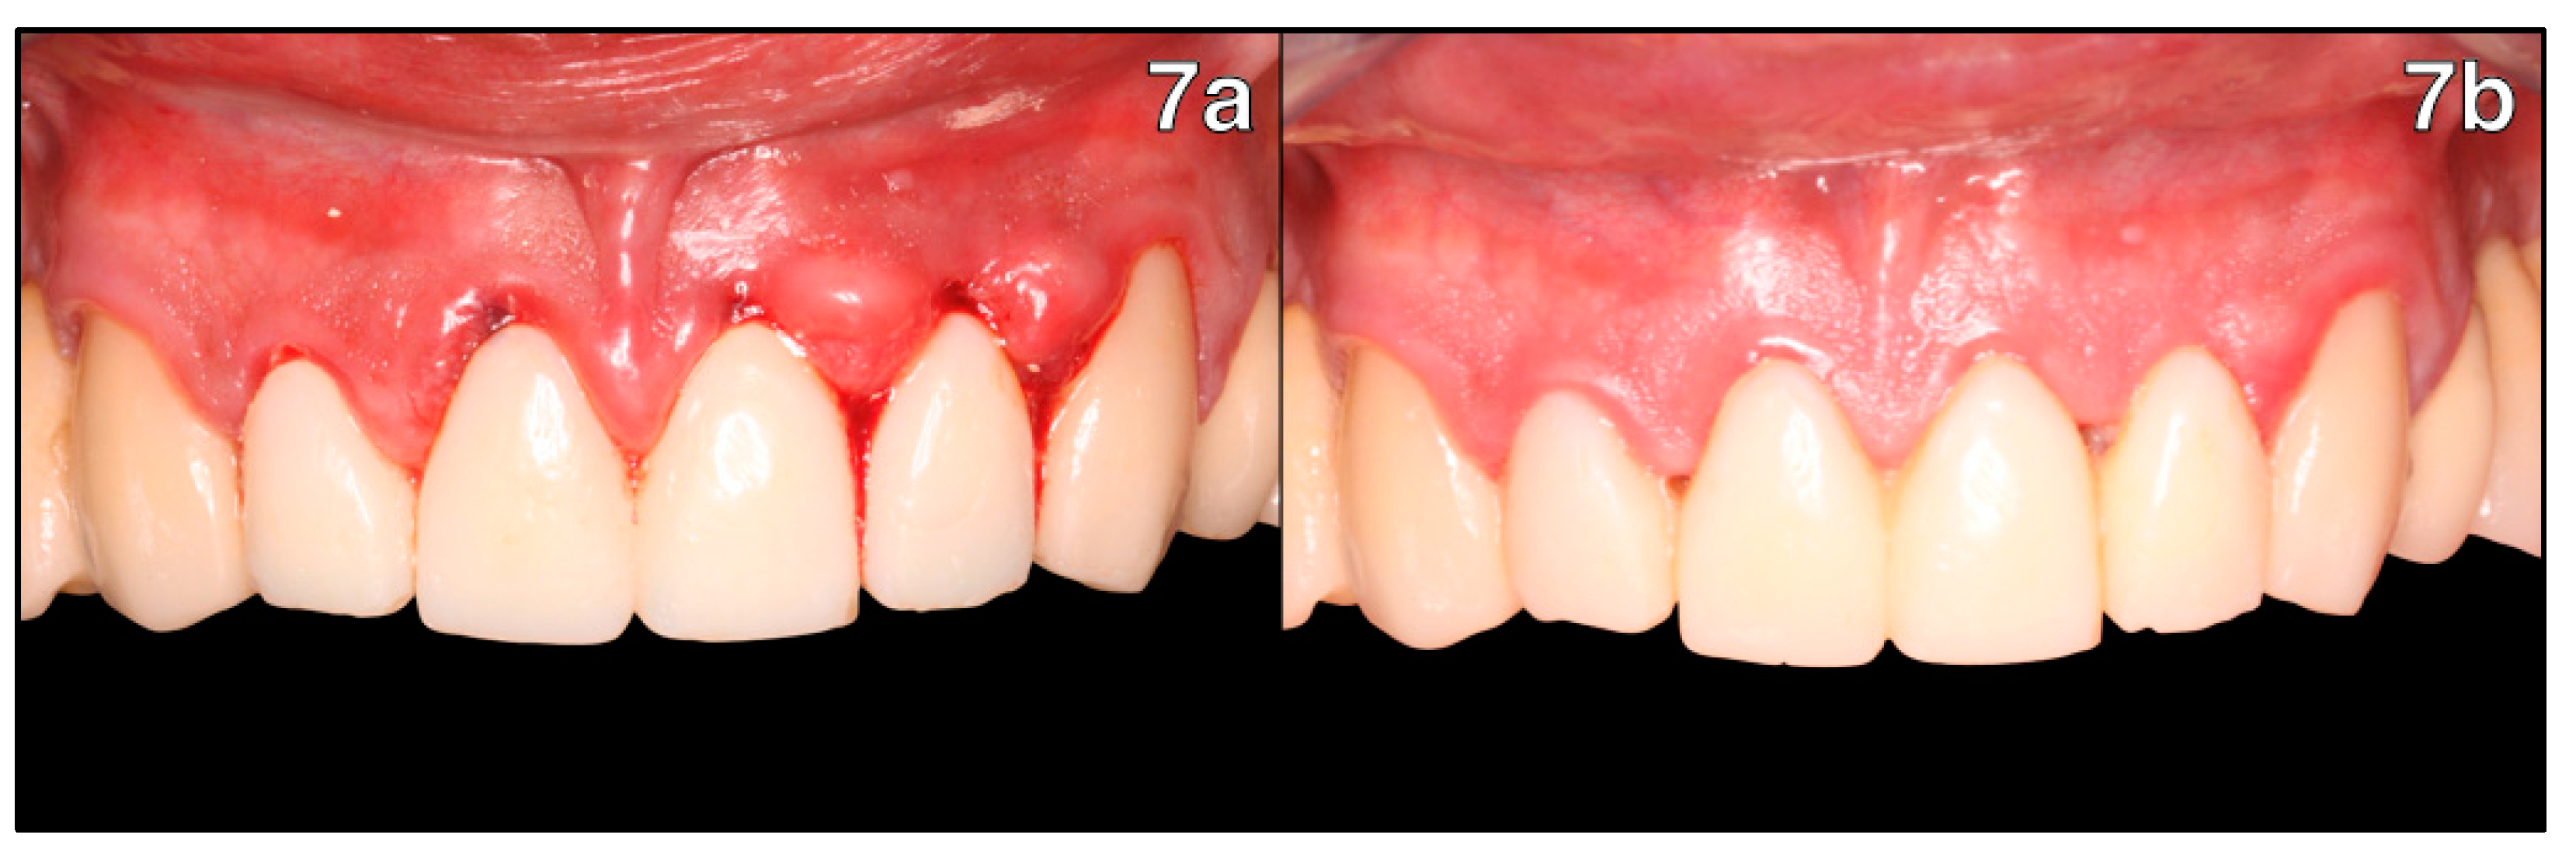

3. Results